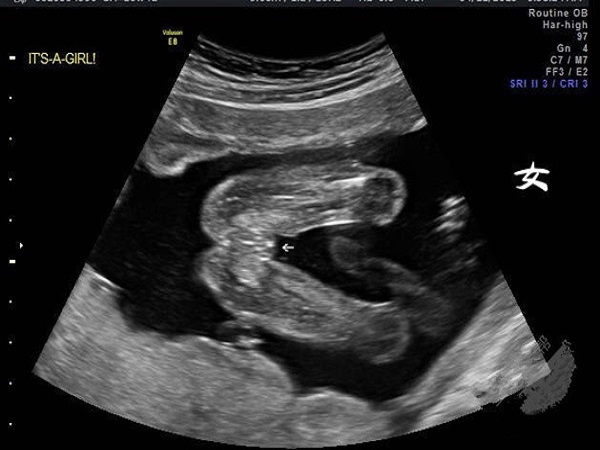

nt图上胎儿尾部平平出现三道杠就说明是女孩

1、看nt图

女孩:如果孕妇怀的是个女孩的话,那么nt检查报告单上图片就会有非常明显的三道杠,一般来说这三道杠会出现在胎儿的尾部,另外胎儿的两腿之间如果出现三条白线的话,也大概率是个女孩,因为这是女宝宝生殖器官的表现;

男孩:如果孕妈妈怀的是个男宝宝的话,那么nt图上胎儿的尾部就是翘起的,另外两腿之间还可能会出现亮点,这就是男孩生殖器的特征。

综上所述,nt单子女孩三道杠主要就是出现在尾部,如果尾部是平平的并且出现三道杠的话,那么大概率怀的就是女孩。当然除了通过图片进行男女的判断之外,通过nt数值也是非常好的判断方法,有相关需求的孕妈妈可以尝试一下,但是需要注意的是不要太过当真。